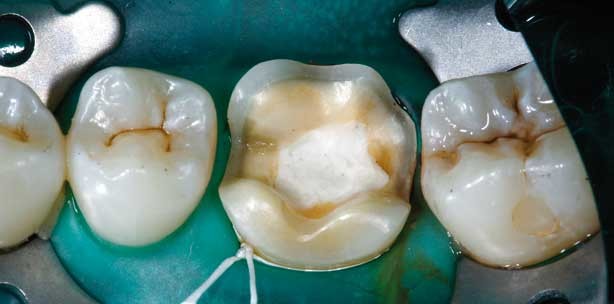

Bei ausgedehnten Defekten verläuft der Kavitätenrand häufig im Bereich der Höckerspitzen (Abb. 1) oder im Bereich okklusaler Kontaktpunkte. Klinisch beobachtet man bei diesen Situationen oft Absplitterungen des Keramikrandes oder benachbarter Schmelzränder. Eine Höckerüberkuppelung kann hier Abhilfe schaffen. Allerdings müssen nicht alle Abschnitte des betroffenen Höckers reduziert werden. Es reicht, wenn die Schichtdicke für Keramik im Bereich des Kontaktes angelegt wird. Die restliche Zahnhart-substanz kann auch bei Überkuppelung einzelner Höckerabschnitte geschont werden. Konservativ ist Kunzelmann bei der Stabilisierung geschwächter Höcker. Sobald die Höcker nur noch aus Schmelz bestehen, d.h. nicht mehr von Dentin unterstützt sind, tendiert er zu einer Höckerüberkuppelung (Abb. 2), obwohl auch eine adhäsive Stabilisierung denkbar wäre. Bei tiefgehenden Kariesdefekten wird oftmals zum Stiftaufbau gegriffen, obwohl hier die Gefahr besteht, dass beim Einbringen die Zahnwurzel gesprengt wird. Hier bietet die Endo-Inlay-Krone, zumindest im Molarenbereich, eine Alternative, die keinen Wurzelstift benötigt (Abb. 3–5). Biomechanische Belastungstests mit Bruchprovokation vs. Titan-Stiftaufbauten zeigten, dass es keine signifikanten Unterschiede zwischen beiden Versorgungsarten (Stift vs. Endo-Inlay-Krone) gibt. Aus Lithiumdisilikat gefertigte Kauflächenveneers, adhäsiv auf Schmelz befestigt und angezeigt für Bisserhöhungen nach Erosionen oder Verschleiß, zeigten klinisch gute Ergebnisse (Abb. 6–7). Der Verzicht auf eine Hohlkehle fördert den Substanzerhalt. Als Tipp zur Befestigung der provisorischen Versorgung vor dem Einsetzen der Kauflächenveneers wies Kunzelmann auf die Möglichkeit hin, den Schmelz an mehreren Stellen punktuell anzuätzen und die Provisorien mit einem „Flowable“-Komposit oder einfacher mit einem „nicht funktionellen“ Bondingmaterial (z.B. Heliobond, Ivoclar) zu befestigen. Auf keinen Fall dürfen Provisorien mit einem Dentinadhäsiv fixiert werden. Da bei der Einprobe und nach definitiver Befestigung meist ein Einschleifen erforderlich ist, ist eine mehrstufige Politur angezeigt. Dafür haben sich elastische Polierer mit Feinstkorndiamantfüllung bewährt, die in der Regel unter Wasserkühlung eingesetzt werden. Abschließend fasste der Referent zusammen, dass Lithiumdisilikat aufgrund der höheren mechanischen Festigkeit dünnere Restaurationen ermöglicht und so wesentlich zu einer deutlichen Schonung der Zahnhartsubstanz beiträgt, wenn Keramikinlays und -teilkronen indiziert sind.